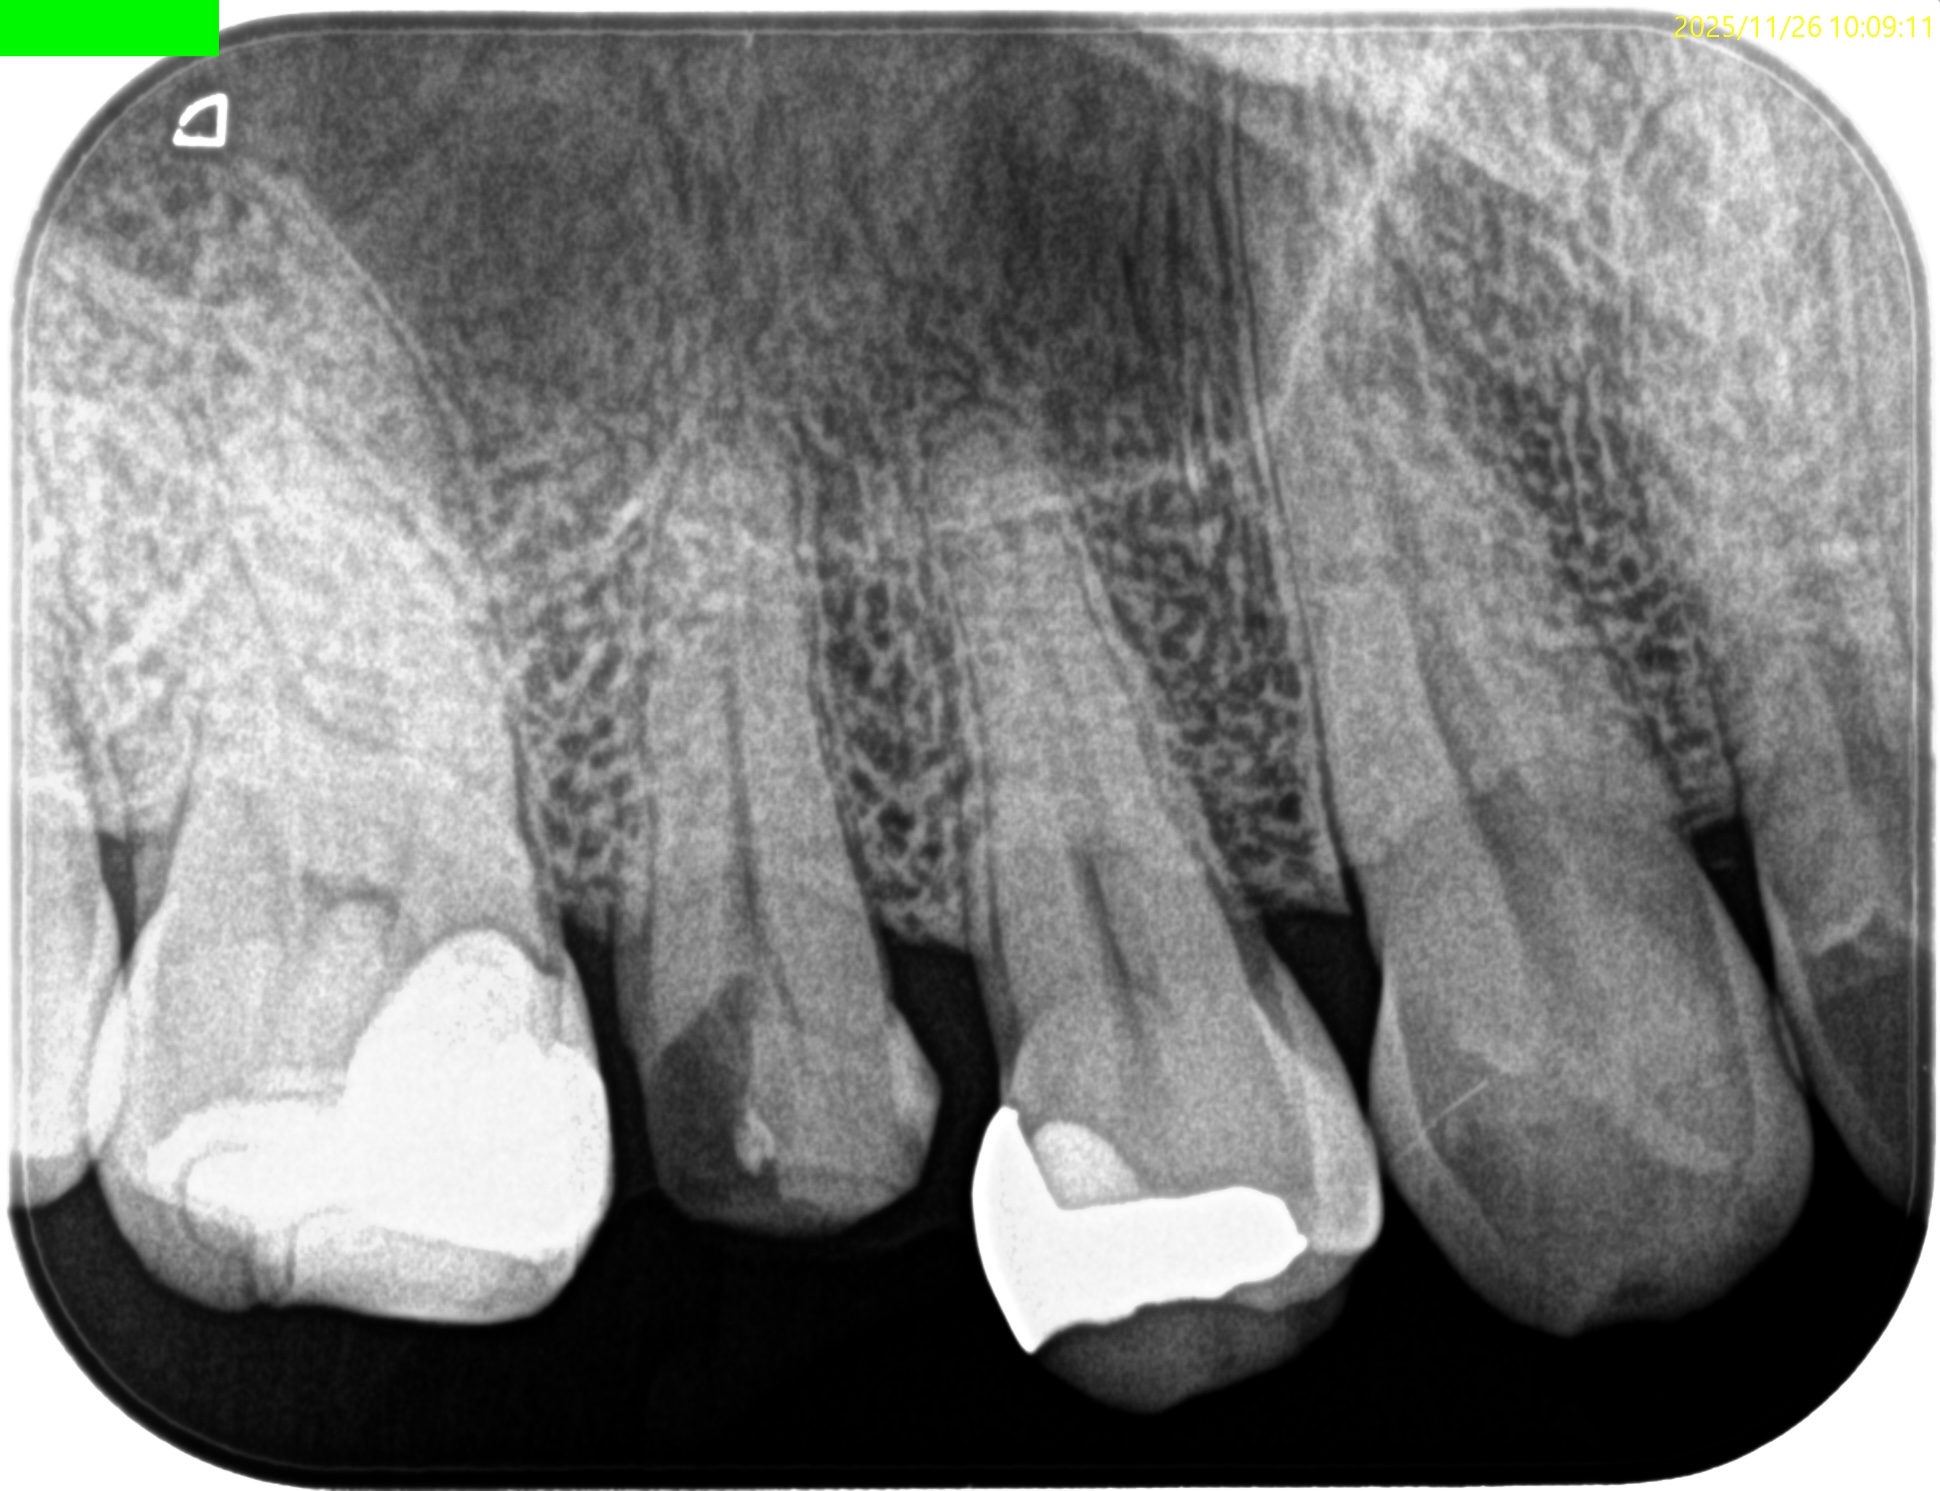

Pre-op Endo test(2025.11.26)

#4に咬合痛があるような…ないようなという感じであった。

病変のない、Initial RCTだ。

Pulp Dx: Asymptomatic irreversible pulpitis

Periapical Dx: Symptomatic apical periodontitis

Recommended Tx: RCT

術後にPA, CBCTを撮影した。